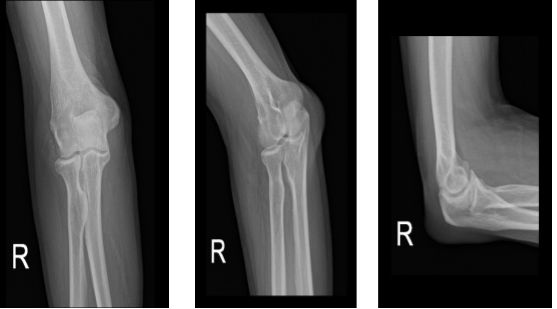

A 65 year-old male patient is here with X-rays of his right elbow and complains of pain from his right elbow. He is unsure how it happened but he said he started to feel the pain 2 days ago. According to his X-ray he has right olecranon bursitis with increased temperature and redness.

After the X-ray was presented and reviewed, we started to discuss treatment options and the patient opted for surgical management. We discussed risks and benefits including injury to adjacent nerves and vessels, infection, bleeding, recurrence, and need for repeat surgery among others. We also discussed systemic complications. The patient understood and signed an informed consent.

Right elbow x-ray